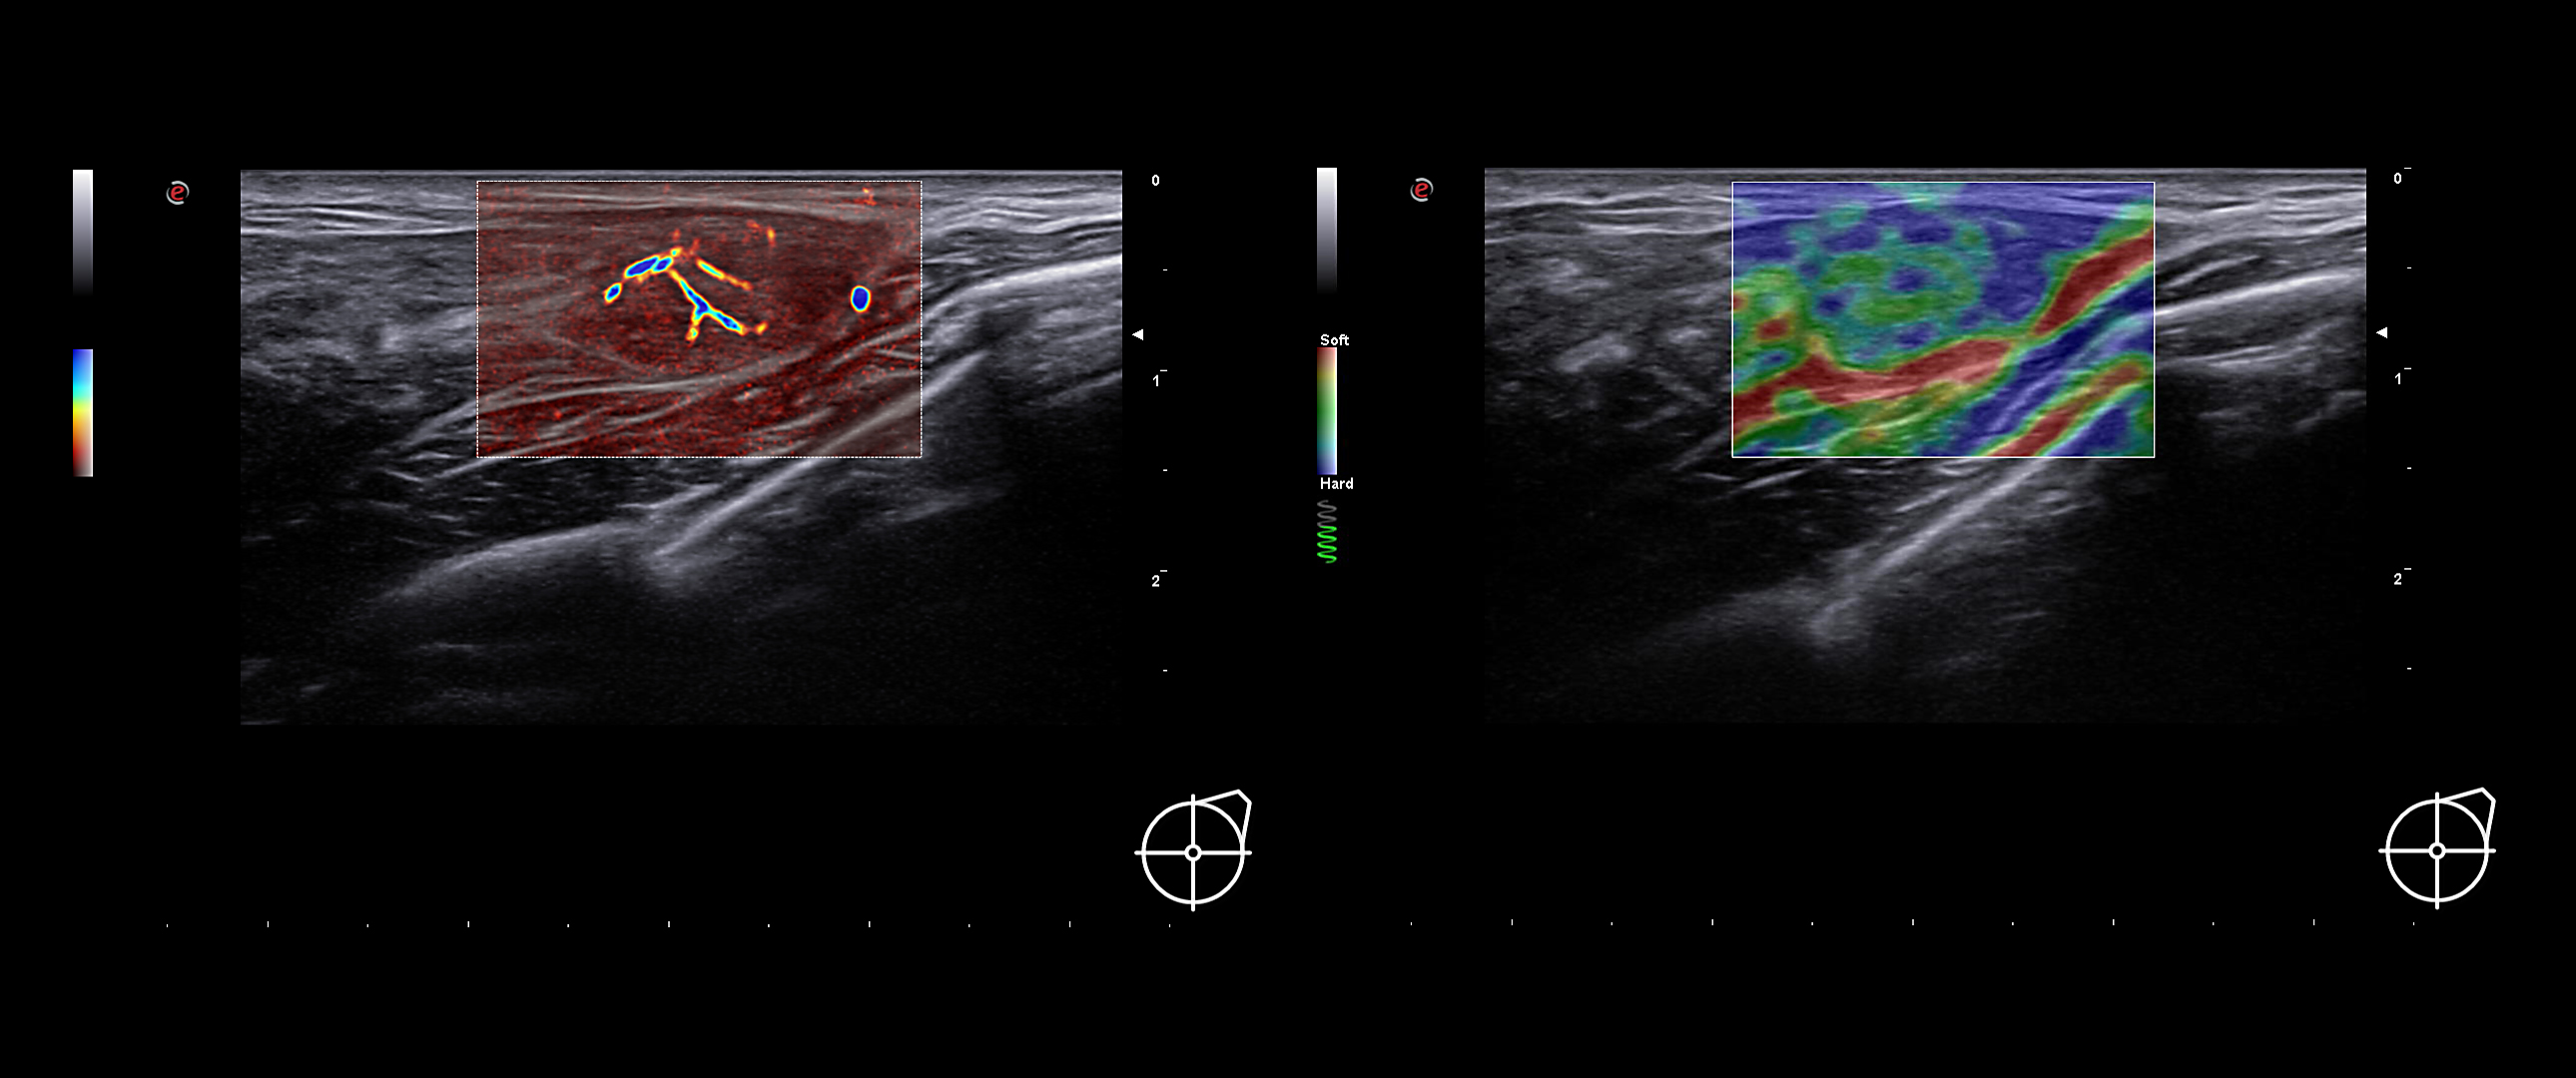

Lesion characterization

Constantly searching for innovative solutions, Esaote’s value proposition for Breast Ultrasound is very broad and is constantly growing.

microV is Esaote’s new Doppler technology with an astonishing degree of sensitivity, even in very small vessels and slow flow detection; ElaXto, strain elastography, for real-time assessment of the relative stiffness of breast tissues; QElaXto 2D, 2D shearwave elastography, for mapping and quantification of tissue stiffness; and microE an algorithm for the enhancement of hyperechoic structures.